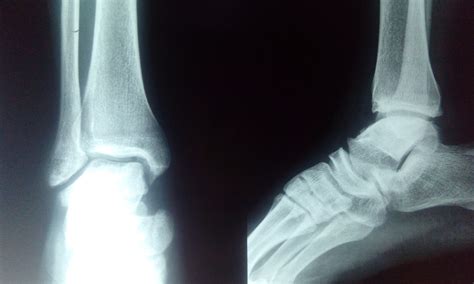

Bilateral Foot Pain ICD 10 Guide Causes Symptoms and Treatment

Bilateral Foot Pain ICD 10 Guide Causes Symptoms and Treatment